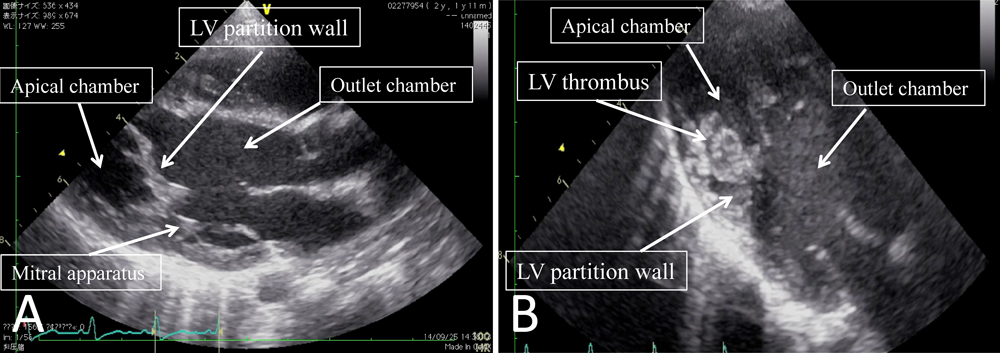

頭部MRIにて左中大脳動脈領域の血流途絶と同領域の脳梗塞を認めた.心エコーでは左室隔壁で隔てられた左室心尖部の動きは良好であり血栓を認めなかった(Fig. 1A*).脳梗塞に対する治療経過中,入院10日目の心エコーで左室心尖腔に11×10 mm大の血栓形成,心尖腔の機能低下と主腔との交通狭小化が見られた(Fig. 1B*).これらの血栓飛散による臓器梗塞,および機能低下による血行破綻を回避する目的で緊急手術を行った.

Pediatric Cardiology and Cardiac Surgery 32(1): 38-42 (2016)

Fig. 1 Preoperative echocardiography

A: At admission. B: 10 days after admission.

第1病日に抜管した.左室副腔機能は速やかに改善し,神経学的所見の悪化もなく,第27病日に軽快退院した.術後9ヶ月時の心エコー上,左室副腔機能は良好に維持され血栓や僧帽弁逆流を認めていない(Fig. 3*).自発運動に左右差を認めず歩行可能となっている.

Fig. 3 Perioperative echocardiography

A: Preoperative echo showed a narrow communication between the two chambers of the left ventricle. B: Echocardiography 1 week after surgery. C: Echocardiography 9 months after surgery showed a wide communication similar to that seen at immediately after surgery.